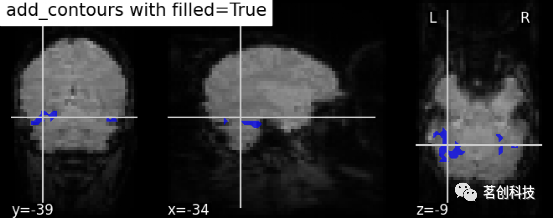

display.add_contours(img, filled=True, alpha=0.7, levels=[0.5], colors=' b '):轮廓填充。

display = plotting.plot_anat(mean_haxby_img,

title="add_contours with filled=True",

cut_coords=[-34, -39, -9])

display.add_contours(haxby_mask_filename, filled=True, alpha=0.7,

levels=[0.5], colors='b')